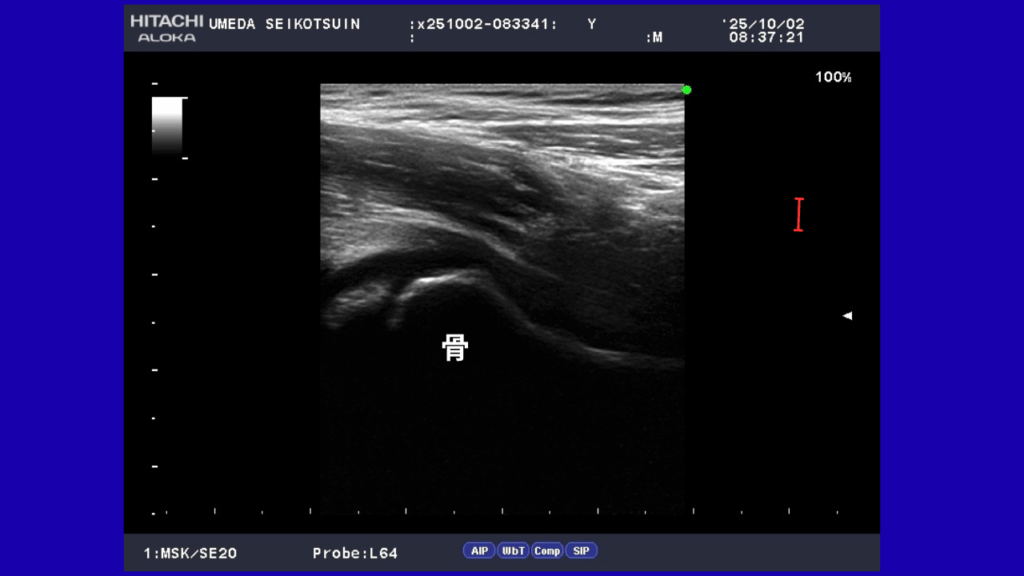

大津市の梅田整骨院では、ケガや痛みの原因をしっかり見極めるために、最新のエコー検査機器を導入しています。

しかし、整骨院で行うエコー検査は、筋肉・靭帯・腱・神経など、レントゲンには映りにくいやわらかい組織を映し出すことができます。

これにより、痛みや不調の原因を詳しく確認することが可能です。

- エコー検査:筋肉・靭帯・神経の様子をリアルタイムで確認できる

大津市の梅田整骨院ではでは、必要に応じてエコー検査を行い、患者さまにも実際の画像をご覧いただけます。